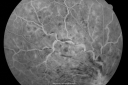

49-year-old woman has central retinal vein occlusion right eye with fluctuating vision and then recently her vision declined and she developed macular edema. I was worried about her angle and you were kind enough to do a peripheral iridotomy and I am dilating her today. Her vision is still poor. VISUAL ACUITY: OD 20/100. IOP: OD 20. There is a peripheral iridotomy, lens is clear, there is no rubeosis. EXTENDED OPHTHALMOSCOPY: OD: Vertical C/D ratio is 0.1. There is 2+ optic nerve edema, 3+ cystoid macular edema. The retinal veins are dilated in all 4 quadrants. The photos confirm clinical findings. Fluorescein angiogram shows some substantial delay in the venous circulation time with no non-profusion. IMPRESSION: 1. PERFUSED CENTRAL RETINAL VEIN OCCLUSION RIGHT EYE. 2. MACULAR EDEMA IN THE RIGHT EYE. DISCUSSION: I explained to the patient that with intravitreal Kenalog there is about an 80% chance of drying up the macula and improving the vision. There is a risk of cataract and glaucoma and a very low risk of infection. I injected the eye today without difficulty with the Kenalog.